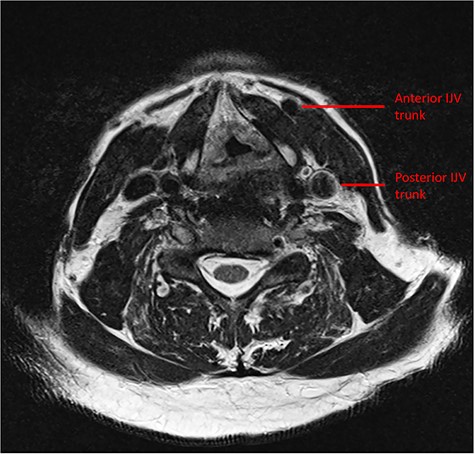

Preoperative MRI demonstrating the duplicate trunks of the left IJV.